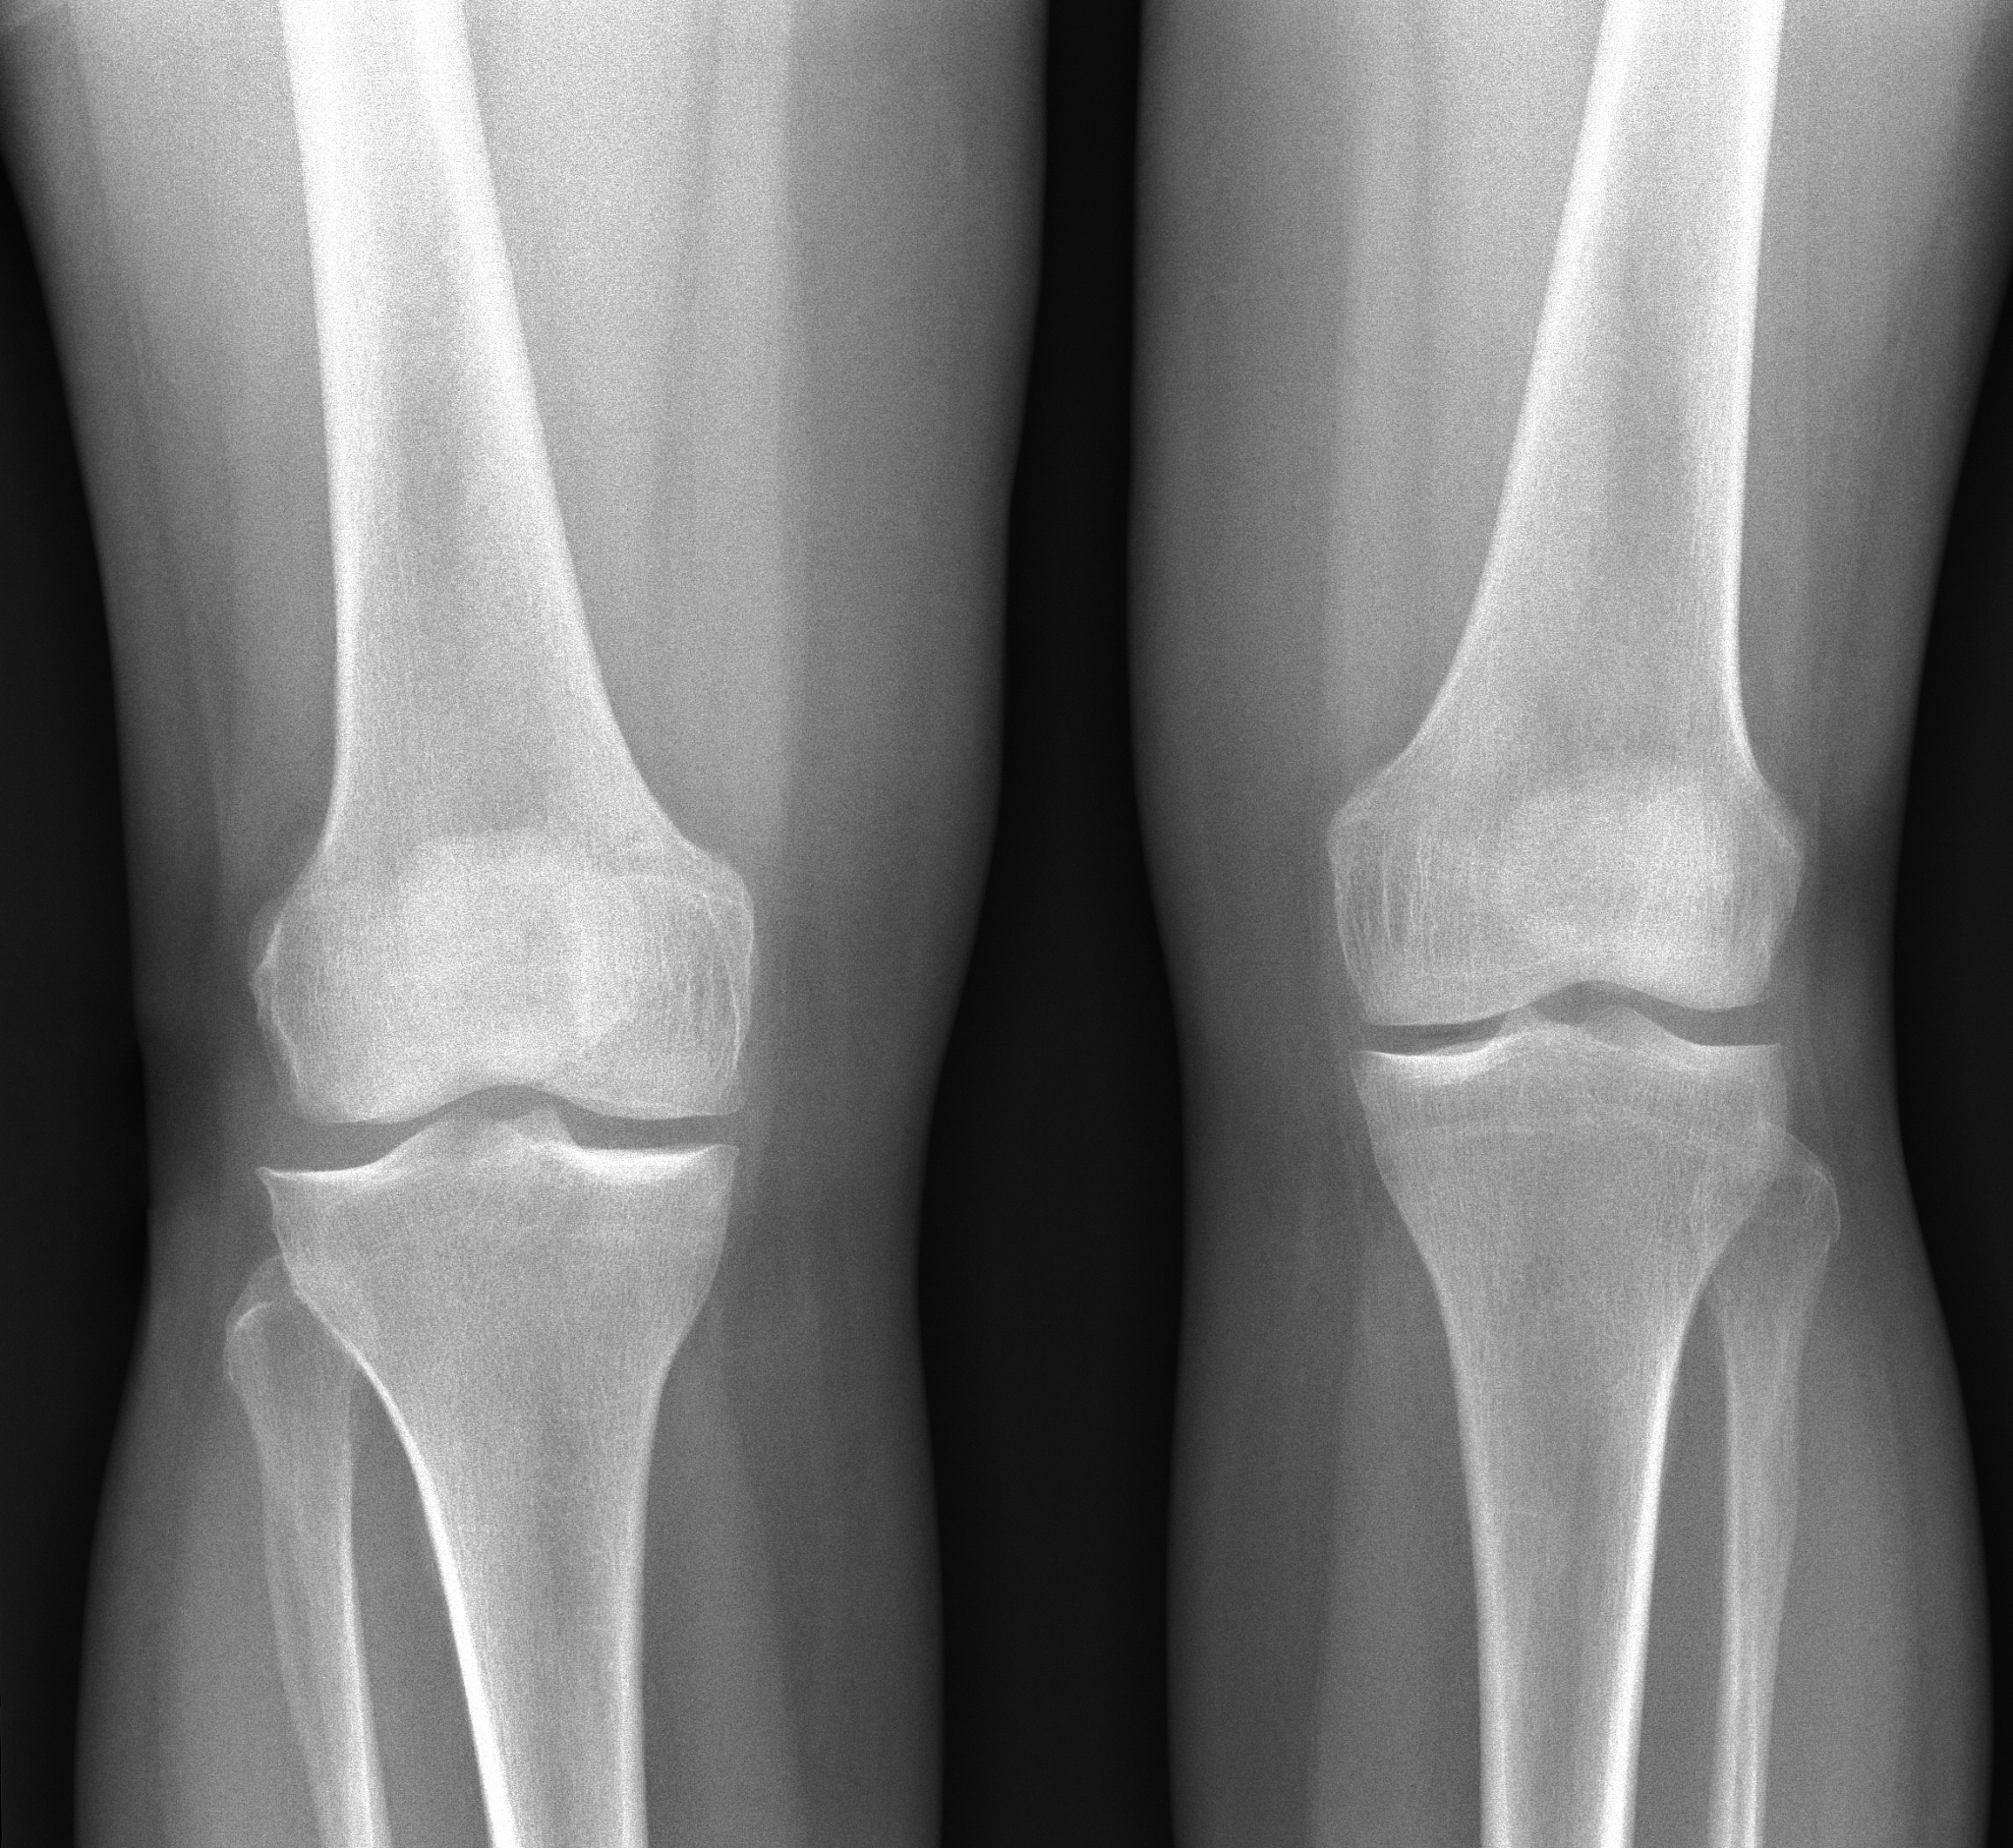

腓骨头上入路治疗后外侧塌陷胫骨平台骨折:优势与适应症

腓骨头上入路治疗伴后外侧塌陷的胫骨平台骨折的优势主要有以下几点:

1. 直接可视化:腓骨头上入路可以直接暴露胫骨平台骨折部位,使外科医生能够直接观察和操作骨折,减少手术操作的难度。